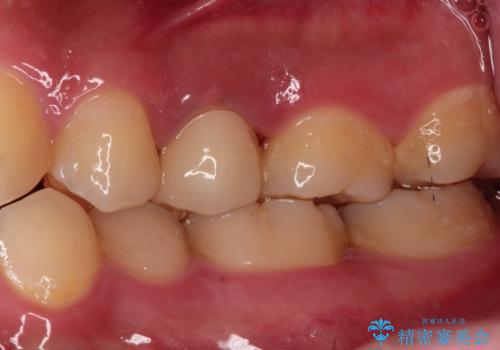

根管治療〜オールセラミッククラウン

- 奥歯がズキズキ痛いことを主訴に来院されました。

根管治療を行なったのち、オールセラミッククラウンにて修復治療を行なっております。